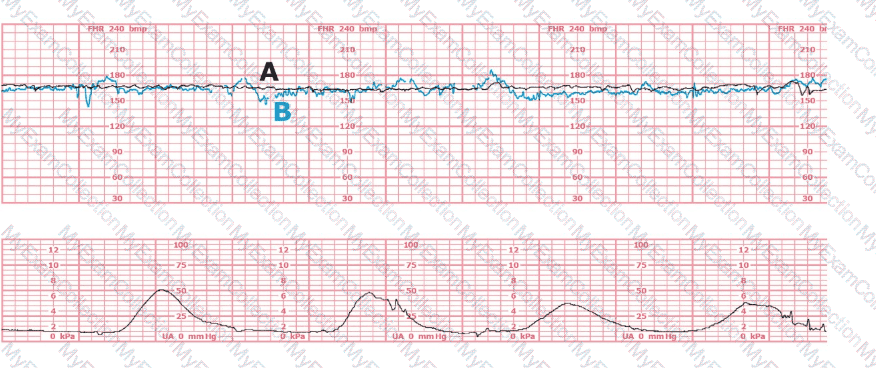

The black pattern represents the heart rate pattern for Baby A. The blue pattern represents the heart rate pattern for Baby B. A possible etiology of the baseline fetal heart rate of Baby A is: